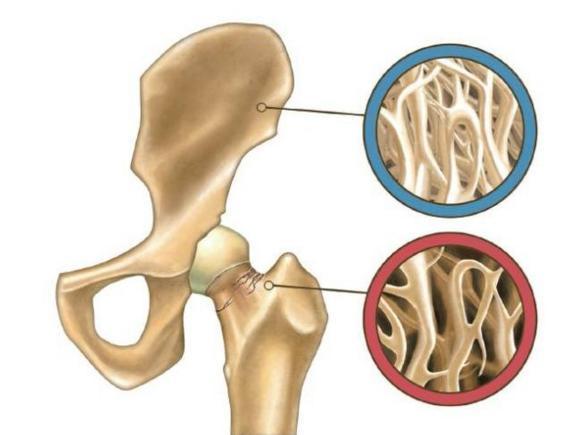

535534a54b764b8aa49a46fde1374d8c.Jpeg7d32551a867649c688226e9eabd3d494.Png

骨質(zhì)疏松治療儀